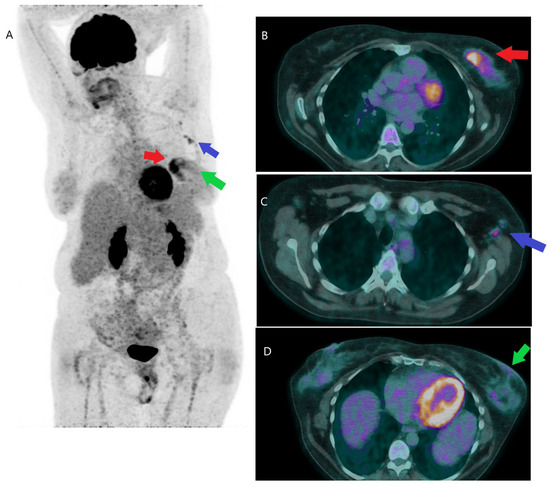

- Gebhart, G.; Lamberts, L.E.; Wimana, Z.; Garcia, C.; Emonts, P.; Ameye, L.; Stroobants, S.; Huizing, M.; Aftimos, P.; Tol, J.; et al. Molecular imaging as a tool to investigate heterogeneity of advanced HER2-positive breast cancer and to predict patient outcome under trastuzumab emtansine (T-DM1): The ZEPHIR trial. Ann. Oncol. 2016, 27, 619–624. [Google Scholar] [CrossRef]

- Dehdashti, F.; Wu, N.; Bose, R.; Naughton, M.J.; Ma, C.X.; Marquez-Nostra, B.V.; Diebolder, P.; Mpoy, C.; Rogers, B.E.; Lapi, S.E.; et al. Evaluation of [89Zr]trastuzumab-PET/CT in differentiating HER2-positive from HER2-negative breast cancer. Breast Cancer Res. Treat. 2018, 169, 523–530. [Google Scholar] [CrossRef]

- Bensch, F.; Brouwers, A.H.; Lub-de Hooge, M.N.; de Jong, J.R.; van der Vegt, B.; Sleijfer, S.; de Vries, E.G.E.; Schröder, C.P. 89Zr-trastuzumab PET supports clinical decision making in breast cancer patients, when HER2 status cannot be determined by standard work up. Eur. J. Nucl. Med. Mol. Imaging 2018, 45, 2300–2306. [Google Scholar] [CrossRef]